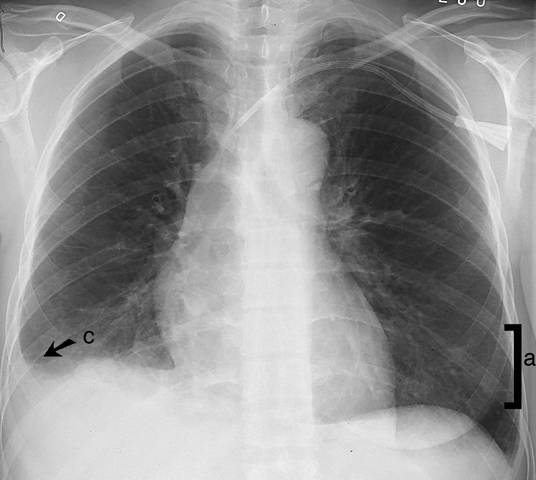

Interstitial oedema in the lungs (PA view). Interstitial oedema in the lungs. Septal lines (a) are 1-2 cm long lines perpendicular to the pleura, best shown in the inferolateral parts of the lungs in the PA view. The condition is associated with pleural fluid (c). For lateral view: see Interstitial Oedema in the Lungs (Lateral View).